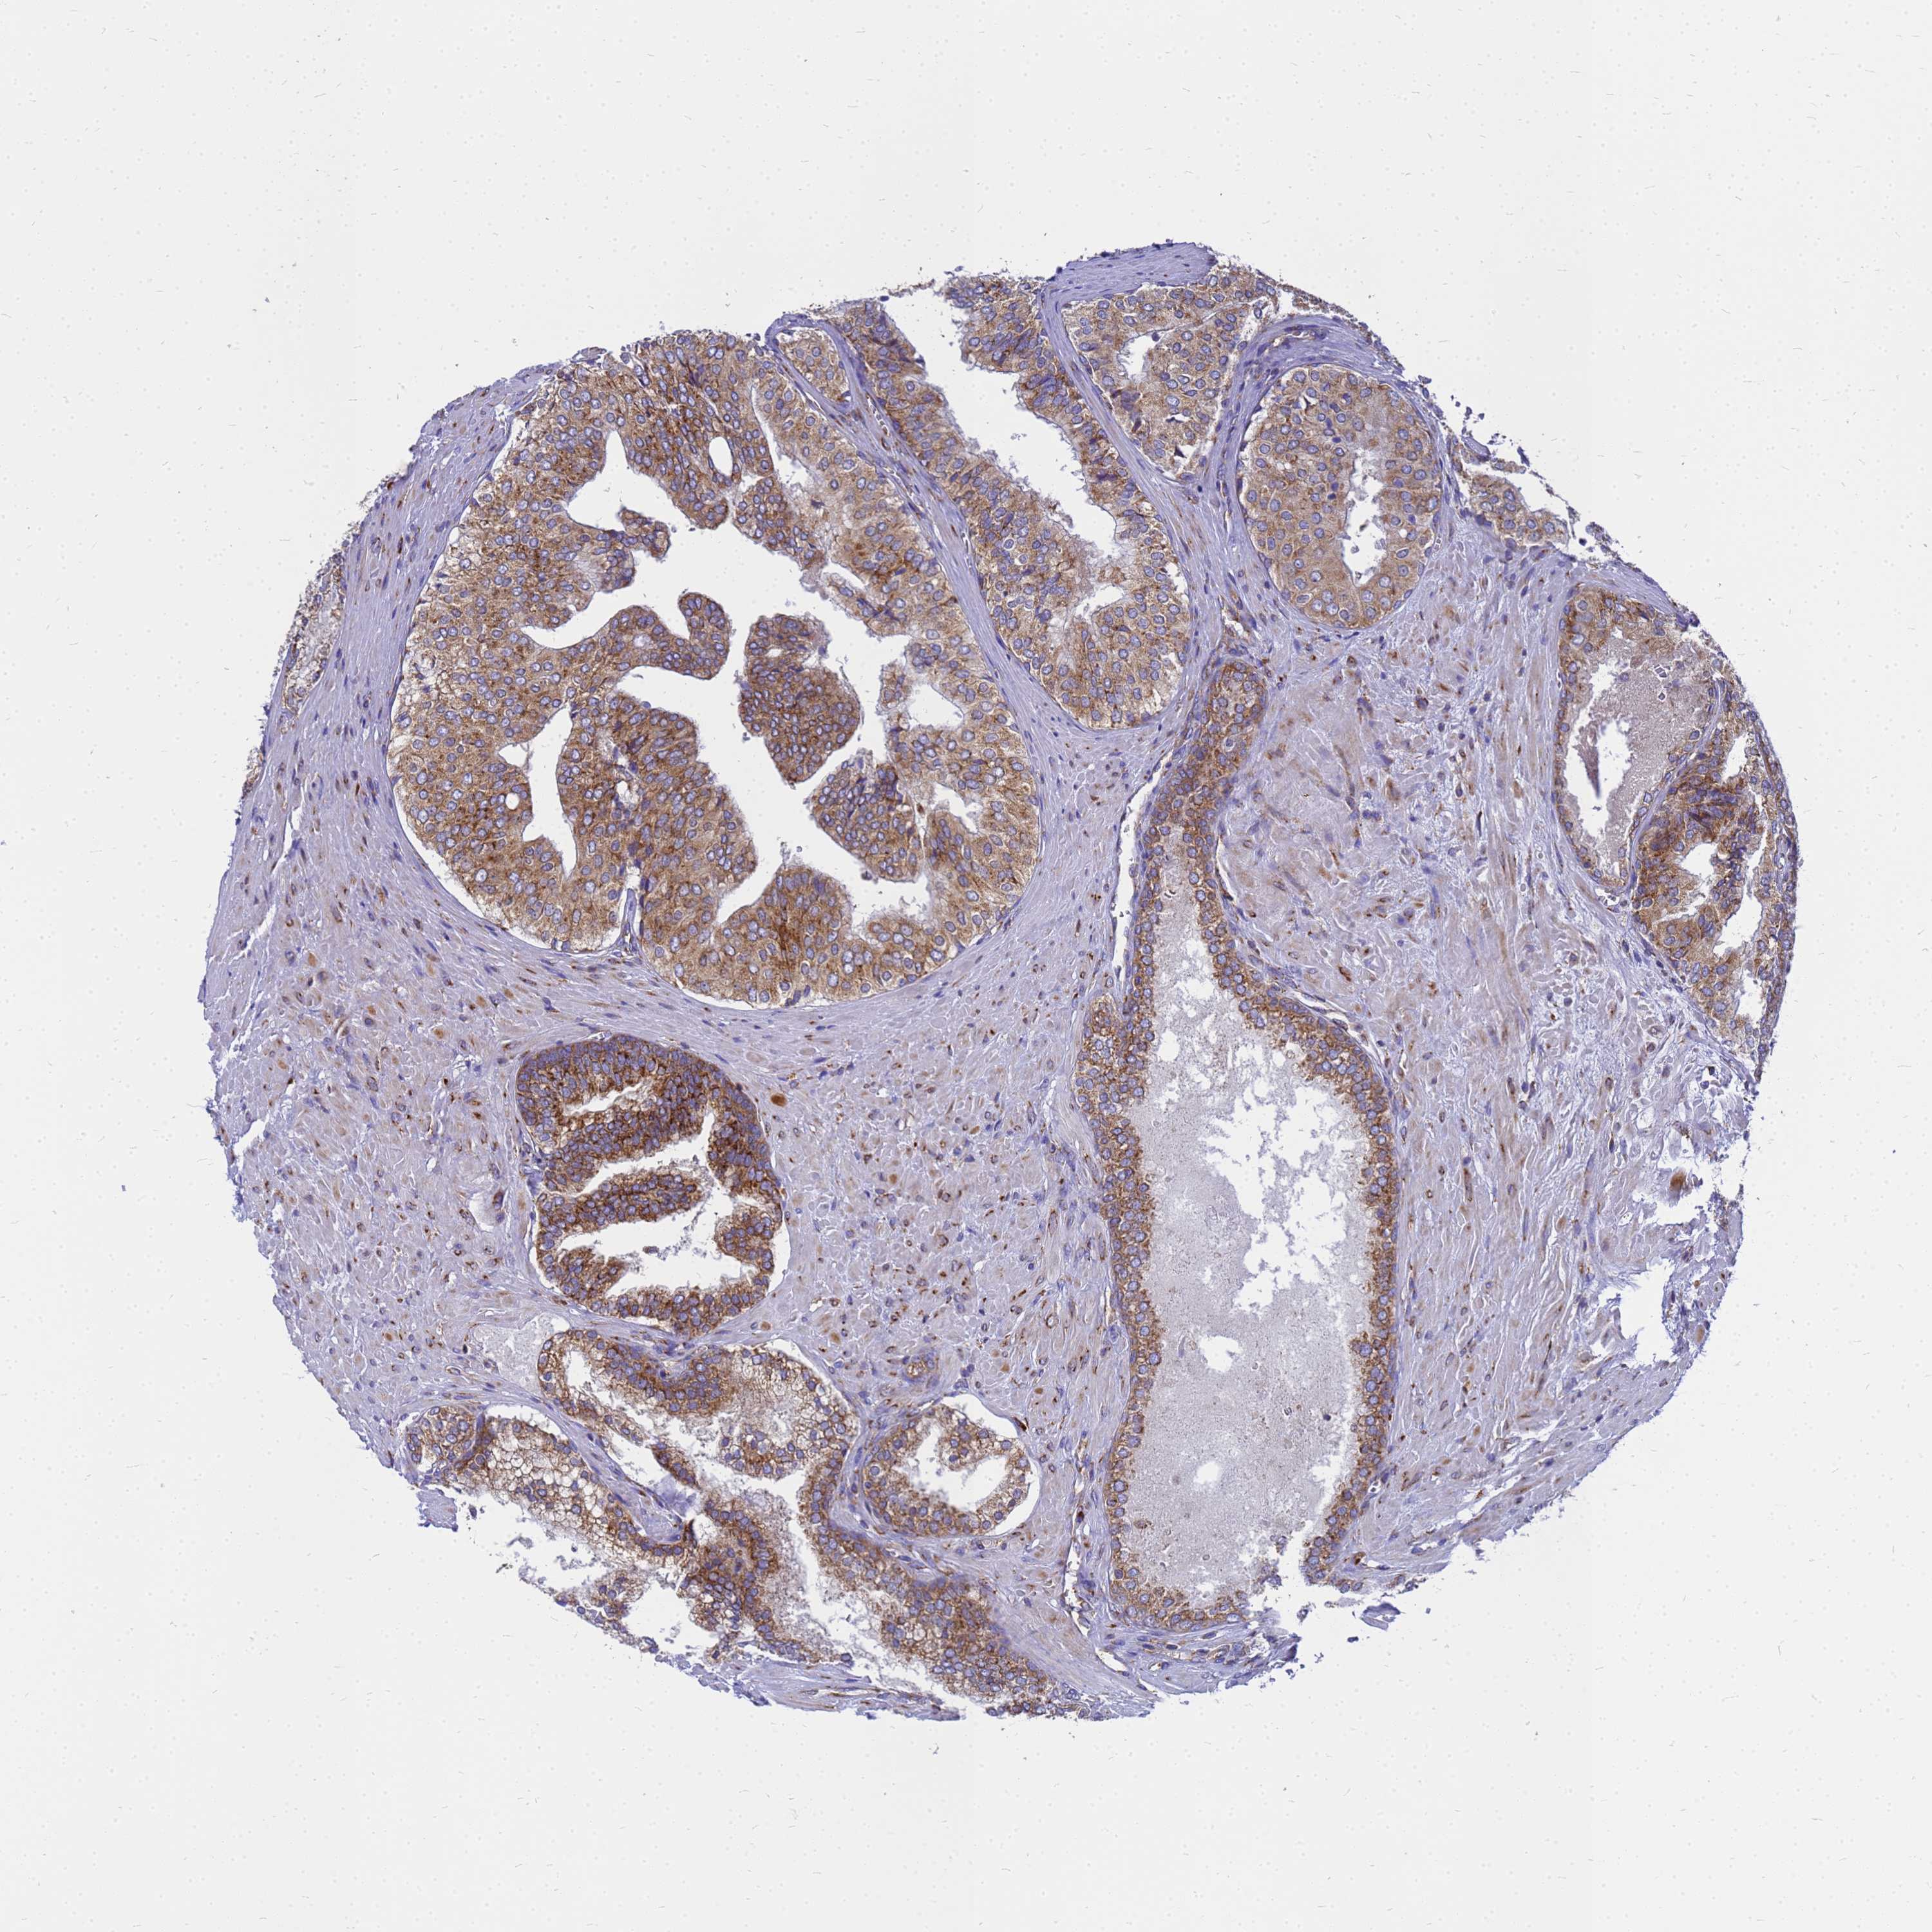

PROSTATE CANCER - Protein expressioni

A mouse-over function shows sample information and annotation data. Click on an image to view it in a full screen mode. Samples can be filtered based on level of antibody staining by selecting one or several of the following categories: high, medium, low and not detected. The assay and annotation is described here.

Note that samples used for immunohistochemistry by the Human Protein Atlas do not correspond to samples in the TCGA dataset.

Antibody stainingi

Antibody staining in the annotated cell types in the current human tissue is reported as not detected, low, medium, or high, based on conventional immunohistochemistry profiling in selected tissues. This score is based on the combination of the staining intensity and fraction of stained cells.

Each image is clickable and will lead to virtual microscopy that enables deeper exploration of all samples and also displays staining intensity scores, fraction scores and subcellular localization as well as patient and tissue information for each sample.

Antibody HPA045101

Staining

High

Medium

Low

Not detected

Intensity

Strong

Moderate

Weak

Negative

Quantity

>75%

75%-25%

<25%

None

Location

Nuclear

Cytoplasmic/membranous

Cytoplasmic/membranous,nuclear

Adenocarcinoma, NOS

Adenocarcinoma, High grade

Adenocarcinoma, Low grade